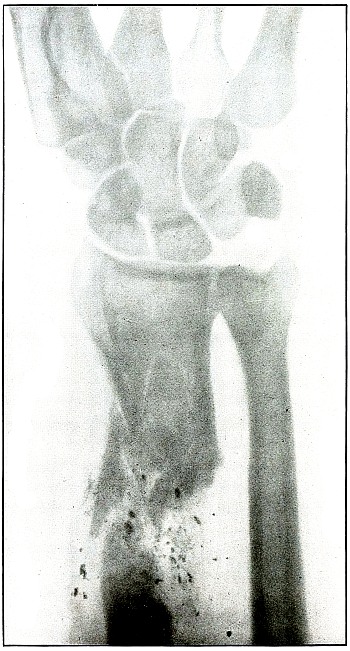

| 41. |

Gunshot fracture, wrist |

92 |

| 42. |

Gunshot fracture, wrist |

94 |

| 43. |

Gunshot fracture, metacarpus |

96 |

| 44. |

Gunshot fracture, phalanx |

98 |

CHEST. |

| 45. |

Gunshot wound, chest |

100 |

PELVIS. |

| 46. |

Gunshot wound, pelvis |

102 |

LOWER EXTREMITY. |

| 47. |